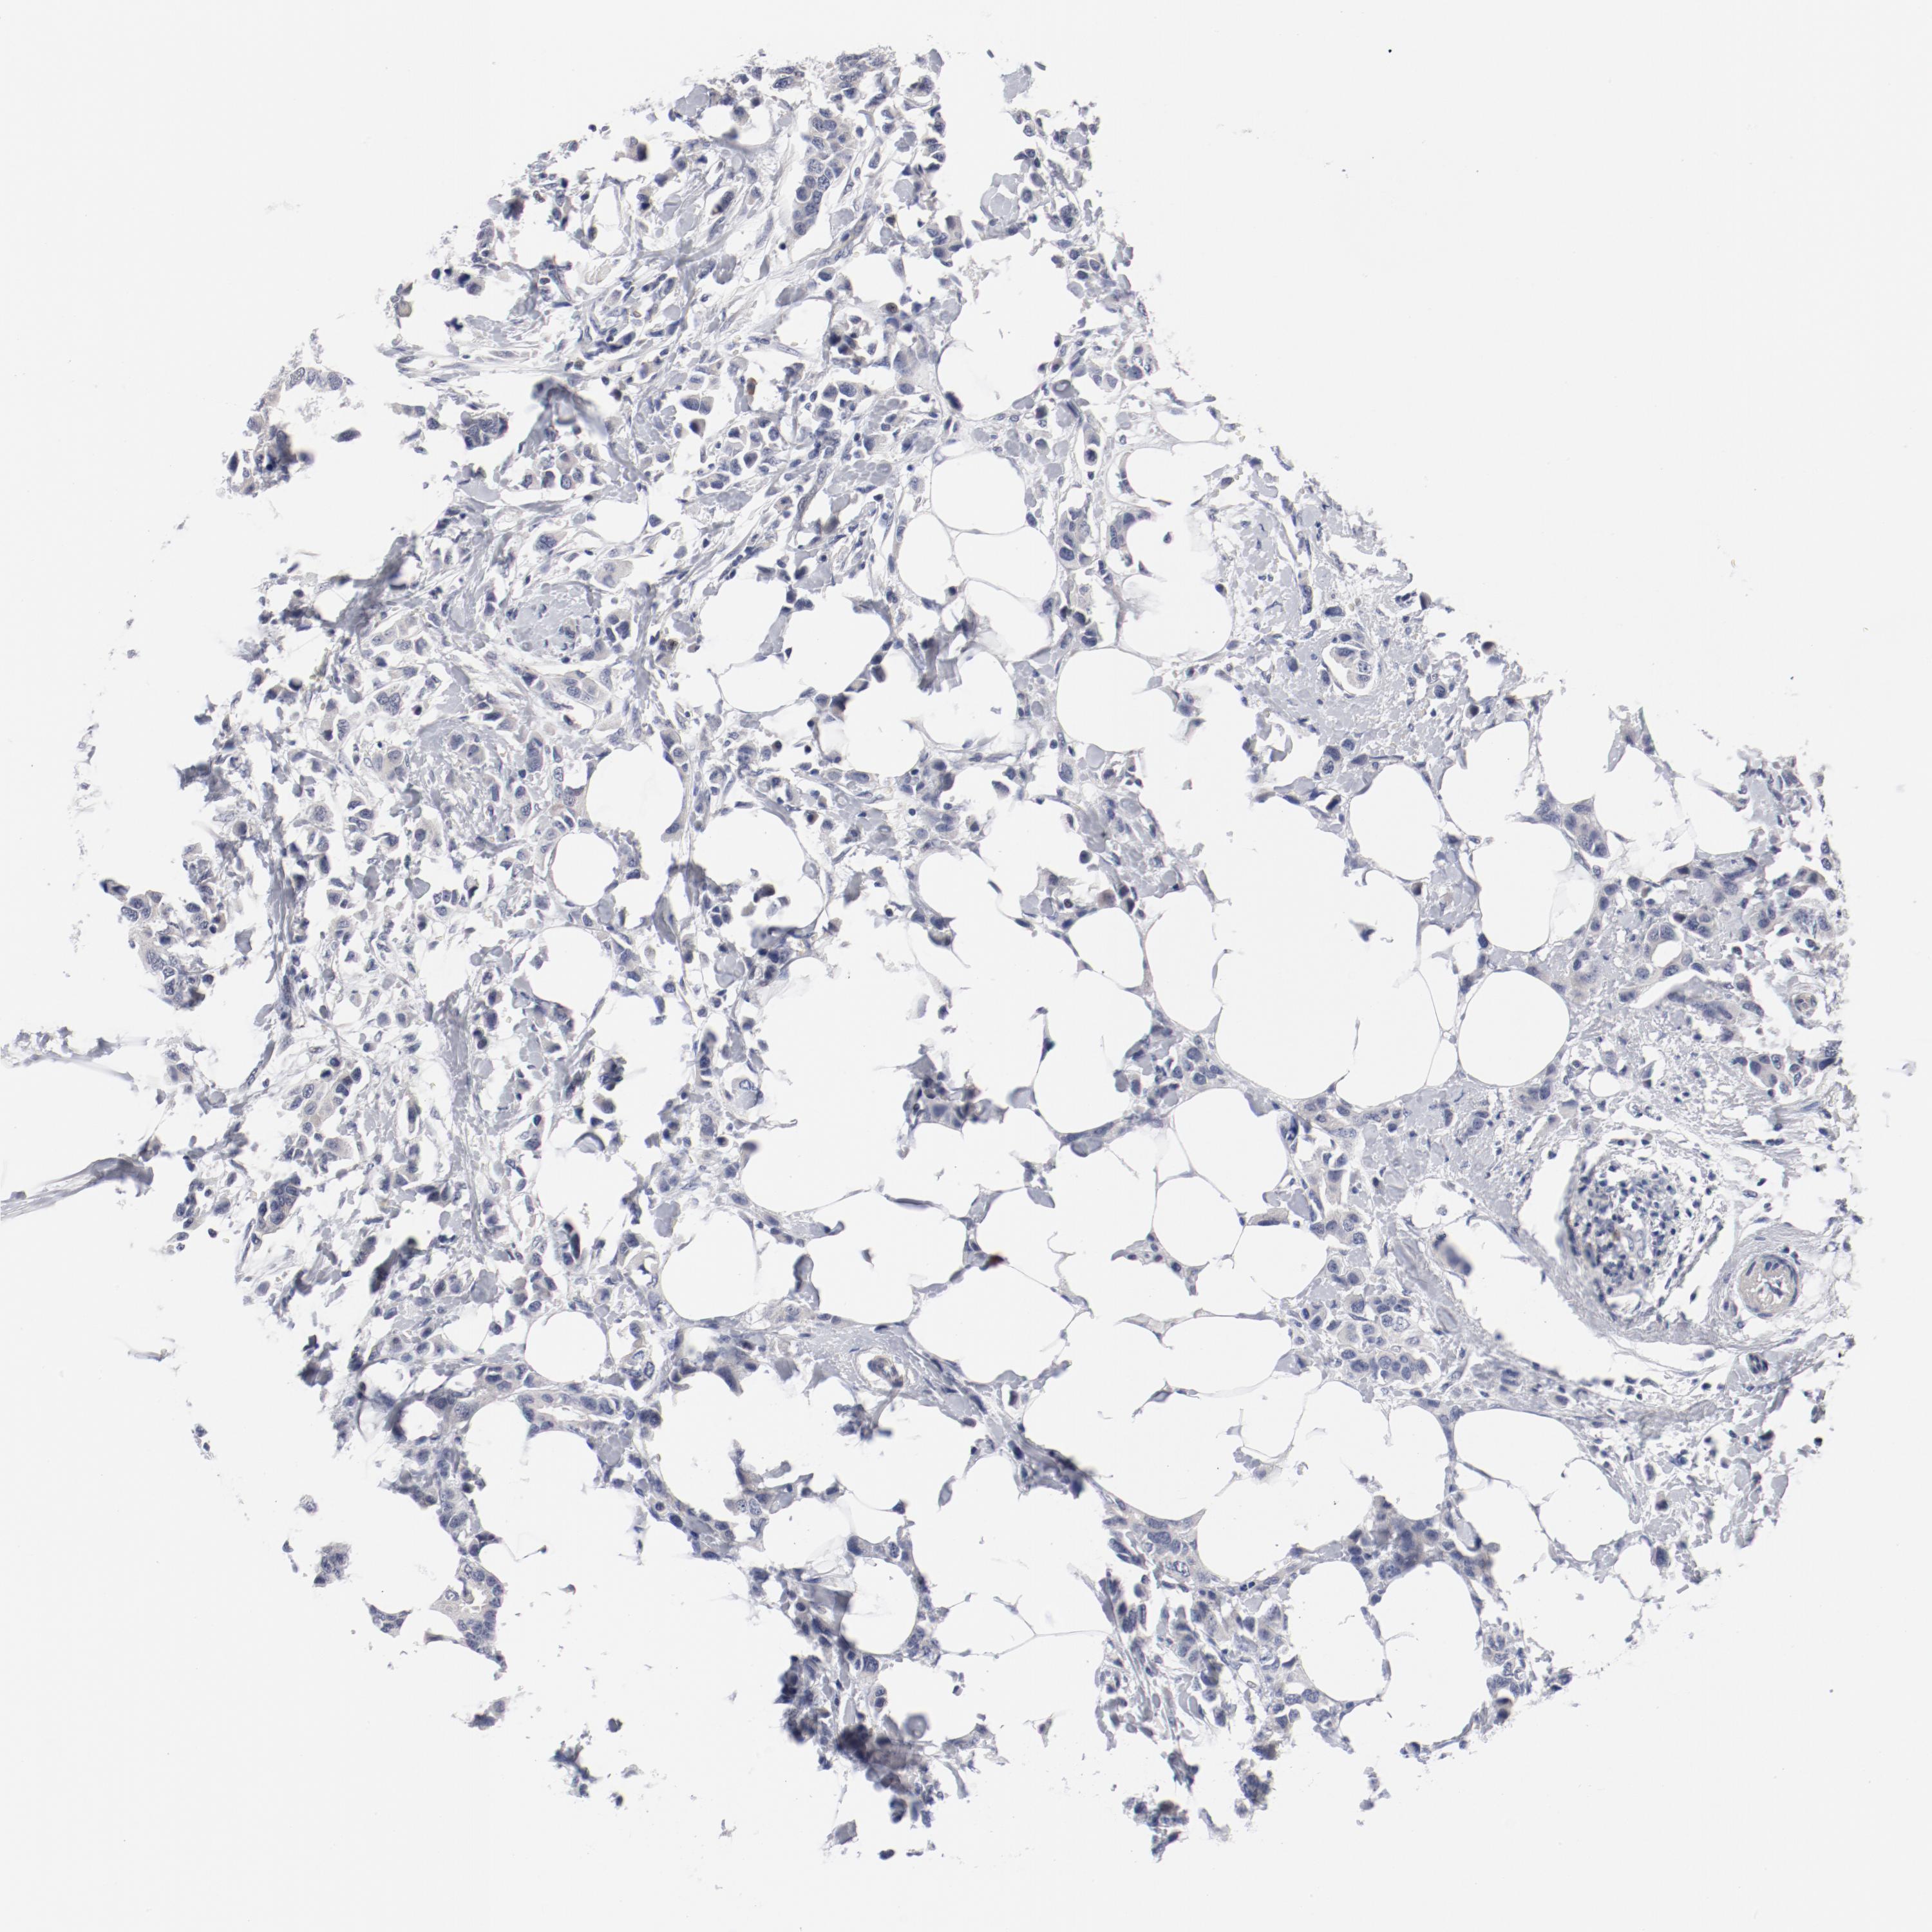

CANCER BREAST CANCER Show tissue menu

BRCA TCGA BRCA VALIDATION PROTEIN EXPRESSION